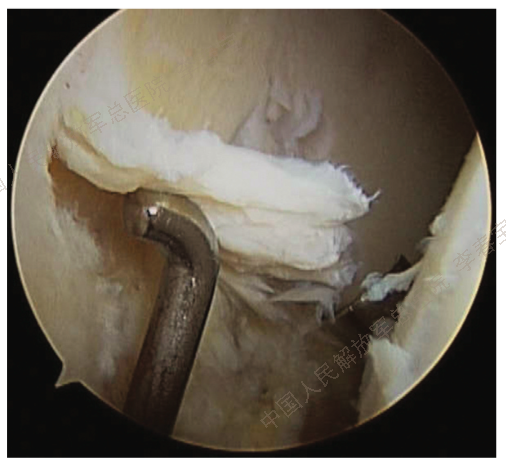

1. 髋臼盂唇损伤

髋臼盂唇损伤是导致髋关节疼痛的最常见原因之一。导致骸臼盂唇损伤的因素很多,包括运动损伤、创伤、年龄、髋关节结构及发育异常如髋臼发育不良等、炎性疾患等,以运动损伤和训练伤最为常见。盂唇损伤最常见于前上方,后方损伤相对少见。从撕裂累计的区域看,盂唇和软骨结合部位最易发生损伤。依据病史、体征、有效的辅助检查或关节镜检查,诊断髋臼盂唇损伤并不困难。通常从事剧烈运动的年轻患者运动后出现腹股沟区疼痛时,可考虑盂唇损伤。非手术治疗可以缓解症状,但不能去除病因,经3-6个月保守治疗无效建议行手术治疗。切开手术的优点是视野好,可在直视下进行修复,多数患者能获得满意的临床结果,但手术创伤大,术后康复时间长。髋关节镜手术创伤小,可直达髋关节中央和外周间室,不仅能处理损伤的盂唇,还可以对髋臼和股骨头颈区骨性异常进行评价和处理。目前关节镜手术盂唇损伤修复是主流方法,主要包括盂唇修整、盂唇修补和盂唇重建。